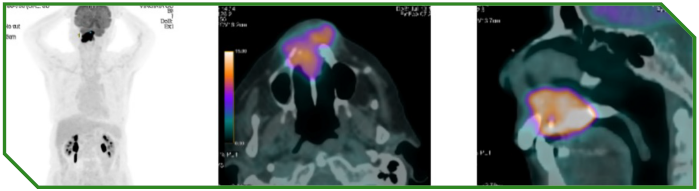

Paciente feminina de 96 anos, funcionalmente independente, diagnosticada com carcinoma espinocelular de cavidade oral localmente avançado e irresecável, com alta expressão de PD‑L1 (CPS 70). Não apresentava condições clínicas para abordagem com quimioterapia sistêmica. Considerando idade avançada, contexto funcional e perfil molecular tumoral, foi instituída imunoterapia isolada como tratamento de primeira linha.